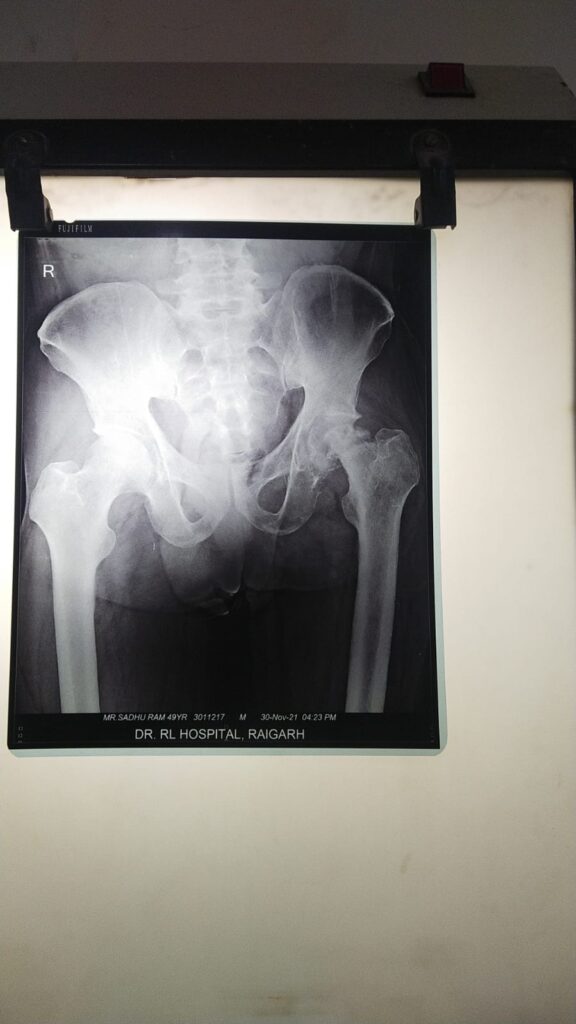

………………..विदित हो की 45 वर्षीय पुरुष (नाम न छापने के शर्त पर ) कूल्हे के दर्द से अत्यधिक पीड़ित था l पिछले छह : महीनों से लगातार असहनीय दर्द की शिकायत थी l इलाज के लिए पीड़ित व्यक्ति कई अस्पतालों का चक्कर काट चूका था l अंततः आशा के साथ पंहुचा डॉ. आर. एल. हॉस्पिटल………….पीड़ित व्यक्ति कई डॉक्टरो के इलाज पाश्चात् राहत नहीं मिलने पर अंततः विश्वास के साथ डॉ. आर. हॉस्पिटल मे हड्डी रोग विशेषज्ञ डॉ प्रशांत से मिलकर अपनी समस्या से अवगत कराया प्राथमिक उपचार